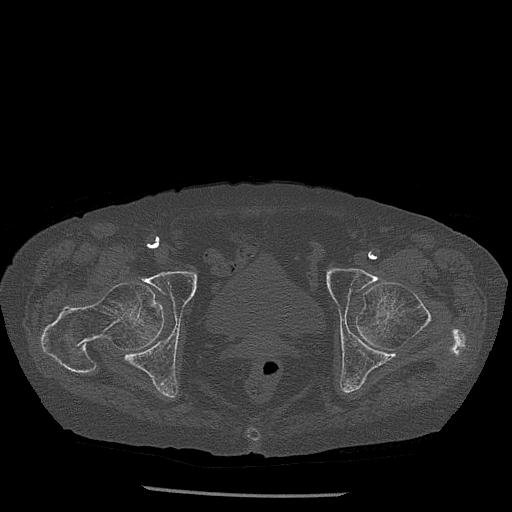

100703 1/27 両股正面+軸 1/29 両股正面+軸 94歳女性 パンソンロン